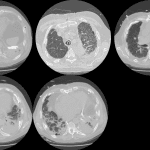

Age: 83

Sex: Male

Indication: Pre-op

Sample ReportBilateral pleural plaques and interstitial coarsening, most prominent at the lung bases. Findings are most suggestive of asbestosis. Consider chest CT for further evaluation.

No definite superimposed focal airspace disease.

Mild cardiomegaly.